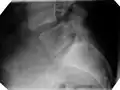

X-ray of a grade 4 anterolisthesis at L5-S1 with spinal misalignment indicated

Classification by degree of the slippage, as measured as percentage of the width of the vertebral body:[14] Grade I spondylolisthesis accounts for approximately 75% of all cases.[6]

- Grade III: 50–75%

- Grade IV: 75–100%